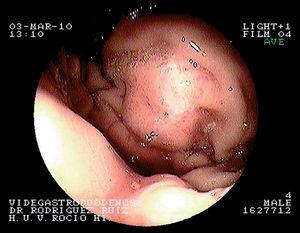

La repetición de la gastroscopia detecta en el pilar amigdalino izquierdo una lesión blanquecina ovalada, indicativa de la presencia de una úlcera revestida de fibrina (fig. 1A). En el fundus se visualiza una lesión amplia de aspecto angiomatoso de aproximadamente 3 cm de diámetro, sin coágulos ni vaso sangrante en su superficie (fig. 2). Se toman muestras para estudio anatomopatológico, el cual revela la existencia de una gastritis crónica activa, y para prueba de ureasa, positiva a los 10 min.

Figura 2. Lesión angiomatosa en fundus gástrico.